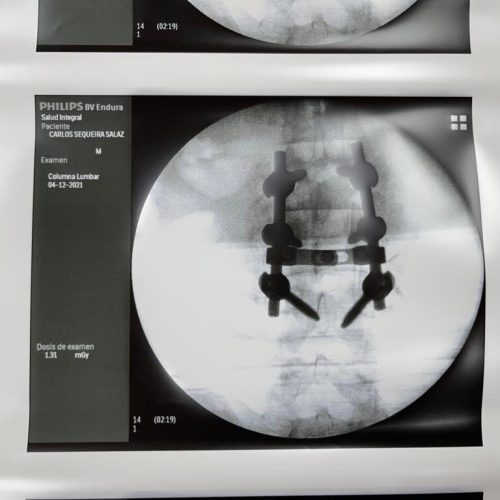

4. Fusión Vertebral (Lumbosacra o Cervical)

¿Qué es?

Cirugía que une dos o más vértebras para estabilizar la columna y aliviar el dolor.

Fusión Vertebral (Cervical o Lumbosacra)

Es un procedimiento quirúrgico que busca estabilizar la columna vertebral uniendo de forma permanente dos o más vértebras. Se utilizan tornillos, barras y, en ocasiones, una caja intersomática con injerto óseo, para que las vértebras se fusionen en una sola unidad sólida.